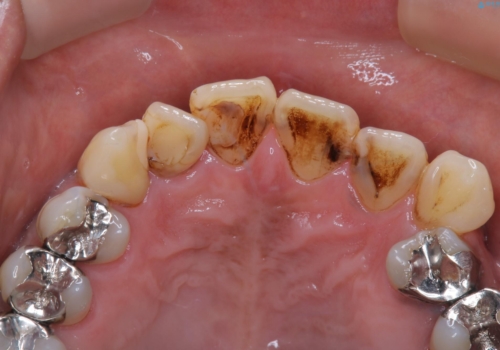

着色がとても多くついていました。

虫歯と着色の色は、同じ黒のため、見分けがつきにくいです。また、着色やプラークで隠れてしまっていることが多々です。

そのため、クリーニングをしっかり行ってから虫歯のチェックをさせていただいています。